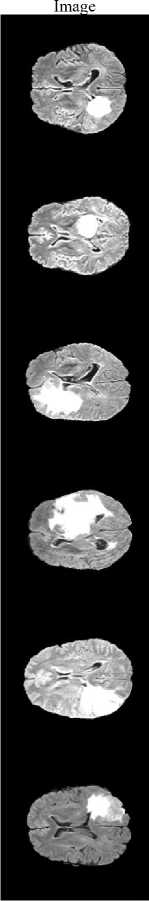

Input

Fig.5. Segmented Image using proposed system

The proposed method achieves a DSC of 0.9907 and a Jaccard Index of 0.9816, demonstrating excellent agreement with expert annotations and confirming that the framework precisely localizes and segments the tumor region rather than over-predicting background. Fig.5 illustrates the segmentation results, where the tumor regions are accurately delineated from the surrounding brain tissues.